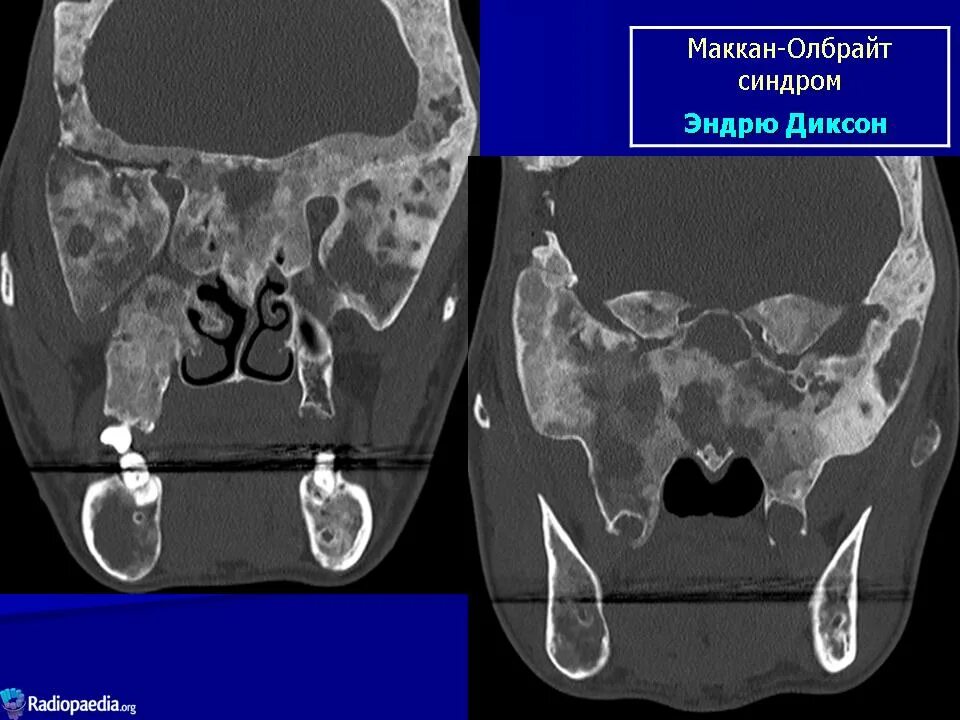

Синдром олбрайта